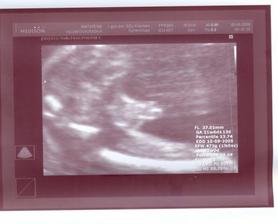

Prvá poradňa bude 2.3.2009. V Poradni všetko OK. UTZ u Dr. Čunderlíka 4.3.2009. Všetko v norme (chvalabohu). Zmenili mi TP zo 4.9.2009 na 13.9.2009. Ďalšia poradňa bude 1.4.2009. V poradni všetko OK. Už len ako dopadnú výsledky z genetiky (7.4.2009). Držte prosím všetci palce. Huráááááááááá AFP testy po opakovaní vyšli super. Konečne budeme mať pokoj. Fuj to bolo dosť zlé ale je to za nami. Už sa len tešiť na bábulko 🙂. Ďalšia poradňa bude 4.5.2009. Snáď uvidíme výbavu 🙂. 25.4.2009 som cítila prvý pohyb (zatiaľ len jeden) 🙂. 29.4.2009 bolo pohybov viacej 🙂)))))). V poradni všetko OK. Asi to bude dievčatko 🙂)))))))))))))))))))))))))). Snáď budem múdrejšia 6.5. 2009 na morfológii. Takže dievčatko to teda nebude 🙂))). Je tam pipík ako hrom. Tešíme sa na Teba synček!!! 20.5.2009 idem na glukózové testy, či nemám tehotenskú cukrovku. Dúfam, že to bude negatívne. Ďalšia poradňa bude 1.6.2009.